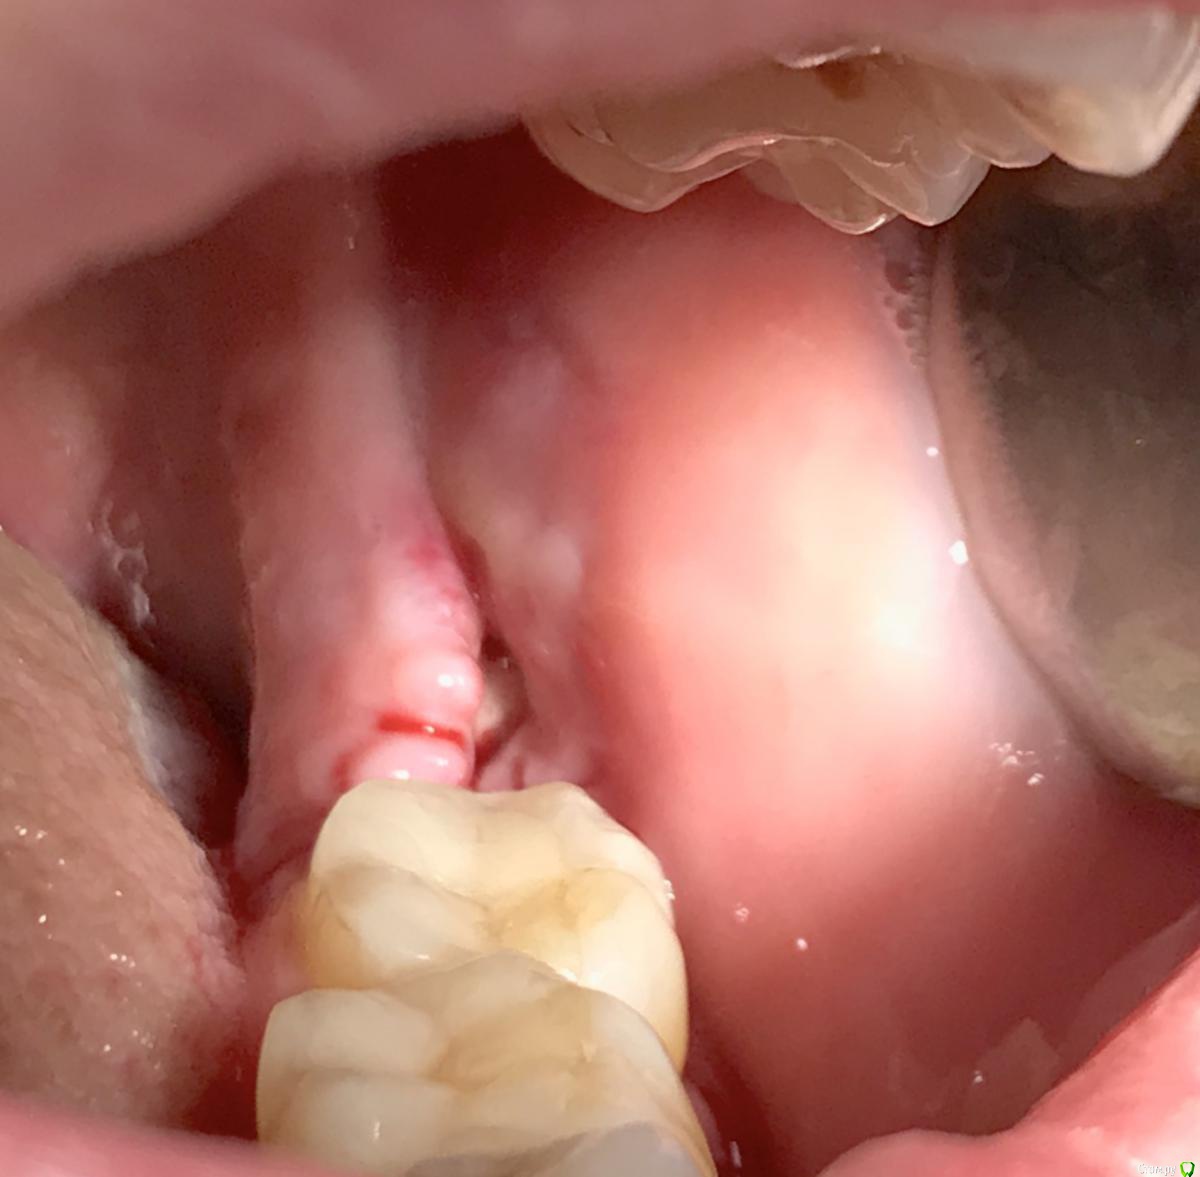

колесников Опубликовано 31 октября, 2017 Автор Поделиться Опубликовано 31 октября, 2017 Ещё раз о закрытии лунки нижних 3их моляров. В лунке 0.5 г графта ,Выделен ретромолярноязычный лоскут и зафиксирован вестибулярно. Края лунки сведены после мобилизации и ушиты двойными узловыми швами. Со слов пациентки болезненность только в день удаления,далее течение бессимптомное. Судя по желтизне кожных покровов шеи,была гематома.Швы удалены через неделю,отмечается расхождение краев,нижний лоскут стабилен,герметичность сохранена. Отправлена на домашнее долечивание с антисептическими повязками. Итого: 1 визит. 3 Ссылка на комментарий

колесников Опубликовано 1 апреля, 2018 Автор Поделиться Опубликовано 1 апреля, 2018 (изменено) Бытует мнение,что капсулу фолликула ретенированой 8ки надо удалять . полностью и тщательно. Аргументов я уже не помню,вроде бы как она стремительно гранулирует,затрудняя регенерацию лунки и кажется что то подобное было у меня в начале практики,что я поверил в эту теорию. Но капсула из этого клин случая ,своей плотностью ,эластичностью и крепостью прикрепления язычно,толкнула меня на эксперимент использовать ее в качестве покровного материала. Протокол был обычный :сепарация и экстракция моляра,графт в лунку (1 г), далее вместо ретромолярно язычного лоскута-капсула фолликула (не фиксировалась,т.к. легла без натяжения) ,края сопоставлены и ушиты. Течение без симптомное. Через неделю: открывание рта не затруднено, слизистая без признаков воспаления. Прогнозируемо щелевидное расхождение краев в первой трети,но при зондировании все плотно и эпителизировано. Как обычно 1 визит,но течение без сопутствующих дискомфортных ощущений. Случай единичный,но результат мне понравился,если будут соответствующие условия- стану использовать Изменено 1 апреля, 2018 пользователем колесников 2 Ссылка на комментарий

Irouil Опубликовано 25 июля, 2018 Поделиться Опубликовано 25 июля, 2018 Откуда начинаете выкраивать лоскут? Как избежать травмы язычного нерва?Этого?) 5 Ссылка на комментарий

колесников Опубликовано 26 июля, 2018 Автор Поделиться Опубликовано 26 июля, 2018 (изменено) Рассекаете первично поверхностно ,от края 7ки и назад по складке. Все как обычно чтобы визуализировать 8 ку,но разрез поверхностный для расщепленного лоскута. Раскрыли. Далее варианты, определяете где у вас «подушка» из прикреплённых тканей. Выделяете ее заходя вестибулярно, язычно расщепляете. Дистально-язычно не углубляетесь. Если получился короткий лоскут,мобилизуете в основании,он хорошо тянется.Вчера была Пациентка с тонким биотипом, ни ретромолярно ни язычно не было ничего что можно было выделить. Расщепил вестибулярный лоскут,выделил надкостницу и перекинул ее лоскутом язычно. В общем импровизируйте,но про анатомию не зыбавайте. Изменено 26 июля, 2018 пользователем колесников 1 Ссылка на комментарий

Irouil Опубликовано 26 июля, 2018 Поделиться Опубликовано 26 июля, 2018 Вот тут я не фоткал "до", так как не было никакого капюшона и не рассчитывал на первичное натяжение. Но язычная стенка лунки оказалась очень низкой, так что я даже не расщеплял, а повернул полнослойный. Два маленьких вертикальных разреза и расщепил надкостницу по язычному краю лунки. 1 Ссылка на комментарий